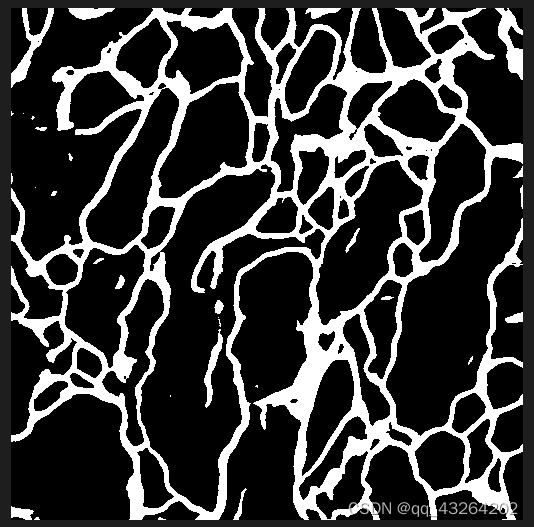

如果想要输出最终的图像为Mask掩膜,不将原图数据作为背景,可以设置opacity参数为1

parser.add_argument(

'--opacity',

type=float,

default=1,

help='Opacity of painted segmentation map. In (0, 1] range.')

最后结果: